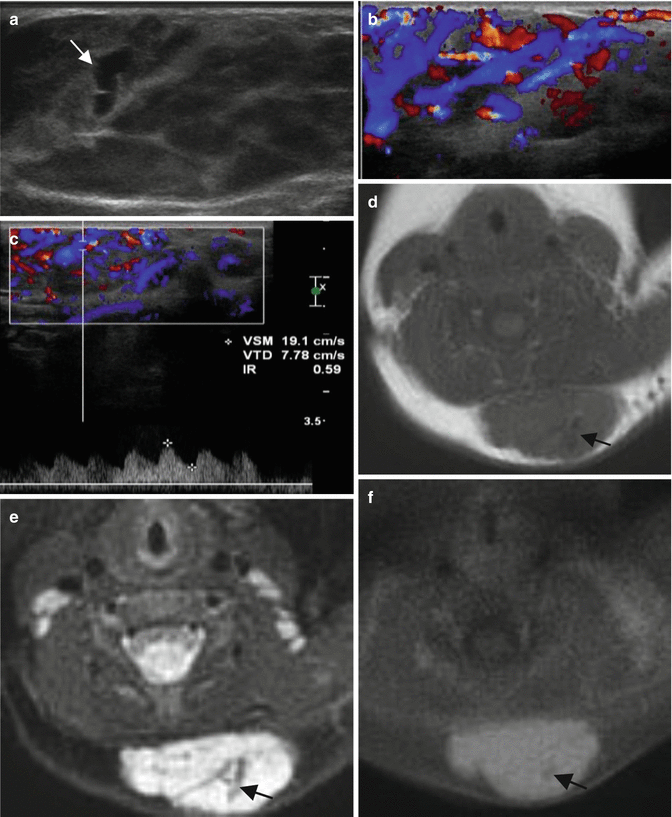

Infantile hemangioma. Nine-month-old boy with subcutaneous mass in his posterior cervical neck. (a) Axial Ultrasound. (b) Axial color Doppler ultrasound. (c) Spectral analysis obtained in tumor center. (d) Axial T1-weighted MR image. (e) Axial T2-weighted MR image, with fat suppression. (f) Axial T1-weighted MR image after Gadolinium contrast administration with fat suppression. (a–c) Ultrasound shows a solid mass with well-defined margins in the subcutaneous soft tissues of the neck (a). The lesion is predominantly hyperechoic with scattered hypoechoic foci that correspond to vessels (white arrow). (b, c) Color Doppler shows hypervascular lesion with low-resistance arteries. (d–f) MRI shows a well-defined, lobulated soft-tissue mass confined to the subcutaneous soft tissues. The mass is isointense relative to muscle on the unenhanced T1-weighted image (d), hyperintense on T2-weighted image (e), and shows uniform enhancement (f). All three images demonstrate small, intralesional signal void foci (black arrows) due to fast flow vessels. There is no invasion of the underlying muscle and no perilesional oedema